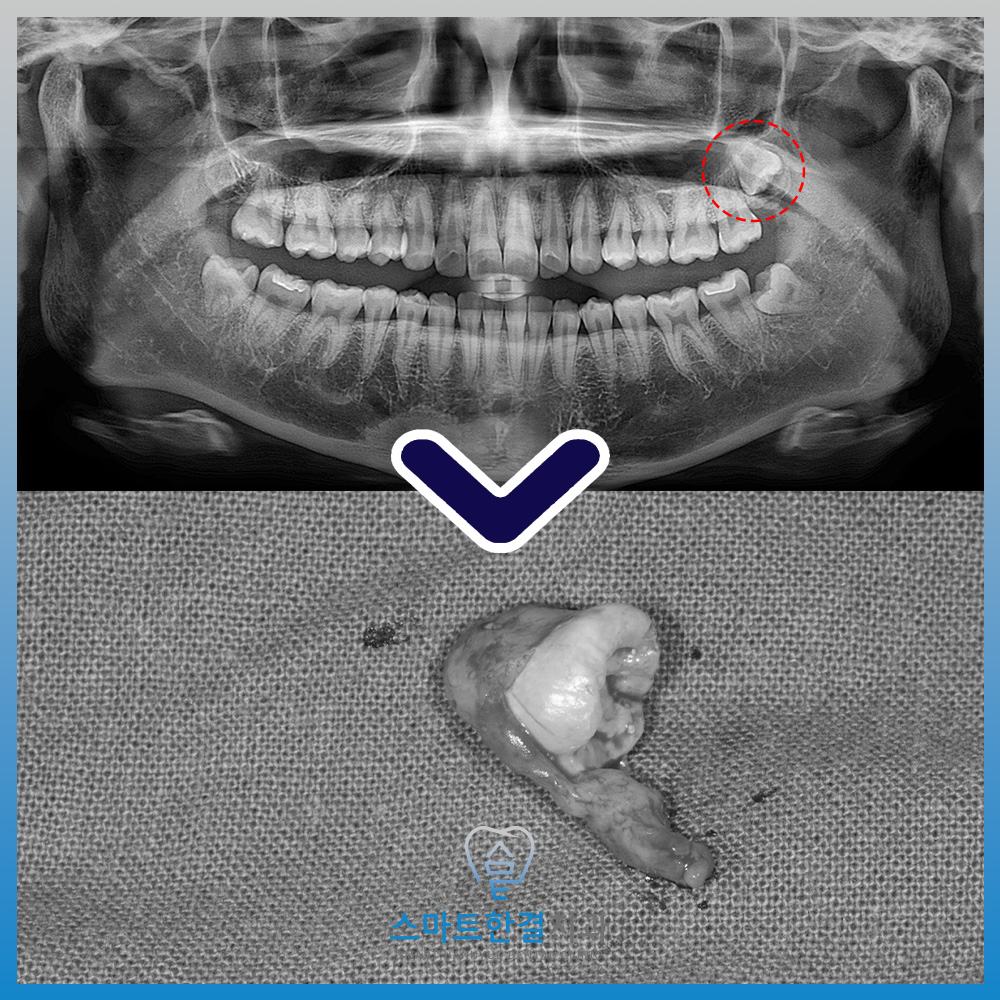

2026.3월

<위쪽 사랑니 낭종 크기 커진 양상>

이후 일 년 뒤 정기검진 위해 재내원하셨는데요.

파노라마를 촬영하여 확인해 보니,

왼쪽 위 사랑니 주변의 낭종이

일 년 전 보다 더 커진 것을 확인할 수 있었어요.

<사랑니 발치 및 낭종 적출>

매복 사랑니 발치를 위해 잇몸을 절개한 후,

주변 치조골을 일부 삭제하여

사랑니가 보이도록 접근했어요.

위쪽 사랑니의 경우 아래 사랑니와 달리

치아 분할 없이도 비교적 원활하게

발치가 가능한 경우가 많아,

해당 환자분 또한 치아 분할 과정 없이

안정적으로 발치를 진행했답니다.

사랑니 뿌리에 낭종이 함께 딸려나온 것을

확인할 수 있었으며,

이는 낭종이 해당 매복 사랑니와

직접적으로 연관되어 형성된 병소였음을

보여주는 소견이었어요.